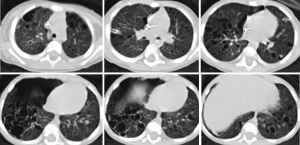

At our institution, treatment for her disease continued with vinblastine for a total of four doses over 4 weeks. She had a continuous air leak and there was concern for a bronchopleural fistula that was potentially exacerbated by continuous suction. A chest tube water seal test resulted in prompt accumulation of extra-pleural air and respiratory decompensation that resolved after the chest tube was upsized from an 8.3 Fr pigtail to a 12 Fr tube. A continuous air leak was present. After extension consultation with national experts, her treatment course was changed to cytarabine 100 mg daily for 5 days on a 4-week cycle and the steroid was weaned. After four doses of vinblastine and two rounds of cytarabine—a total of 7 weeks on chemotherapy agent treatment—she continued to have a continuous air leak and had failed several water seal trials. She decompensated rapidly when the chest tube clotted, requiring transfer to the intensive care unit and chest tube replacement or a second chest tube. CT imaging confirmed extensive, bilateral involvement of lung with large cystic spaces throughout the parenchyma, and a sizeable pneumothorax, despite chest tube drainage (Figure 1). Based on outside consultation and prior case reports that indicated success with pleurectomy, we decided to offer surgical intervention. At 8 weeks of treatment, she underwent a video-assisted thoracoscopy and total pleurectomy. She was extubated on postoperative day 1. She continued to have an air leak and a small pneumothorax for several days after surgery until pleural apposition and resolution of her air leak were achieved at postoperative day 7. We maintained her chest tube to suction for another 7 days and her chest tube was removed successfully after a water seal test.